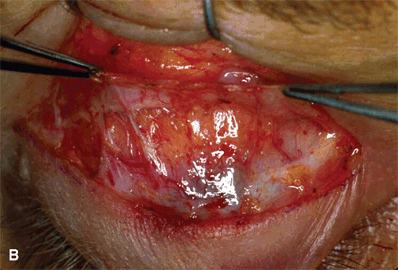

Figure 16-4A and B. The lid margin suture is then released and gentle retrograde digital pressure is applied onto the globe to prolapse the preaponeurotic fat pad. The yellowish fat pad can be seen bulging forward and distending the overlying thin, translucent orbital septum. The tip of the instrument is pointing at an intact orbital septum, with its attachment to the aponeurosis. A horizontal snip with scissors directed perpendicularly is used to buttonhole the orbital septum above its fusion with the aponeurosis.